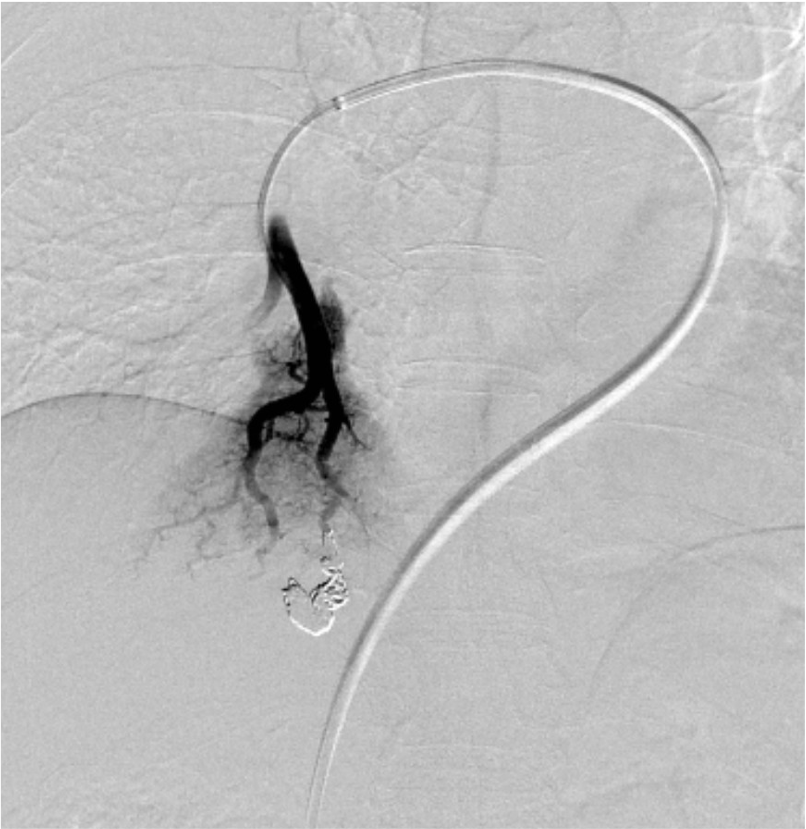

尿路の精査目的で施行した単純CTで, 偶発的に右肺下葉に肺動静脈奇形を認めた. 症状はなく, 流入動脈径は細径であったが, 今後, 脳梗塞などの神経学的合併症を引き起こす可能性があることから, 血管塞栓術の方針となった. 治療方針決定のため, 造影CTを施行した. 造影CTを参照して血管造影, コイル塞栓術を施行し, 良好な治療効果が得られた.

肺動脈は体動脈よりも壁のコンプライアンスが高いため伸縮しやすく, また肺動脈内では線溶系が亢進しているため血栓が溶解されやすい状態とされる. そのため肺動静脈奇形では塞栓術後の再発率が高いことが報告されており, 再発を予防するためには適切なコイルサイズ, 十分な量のコイルを使用するtight packingが必要である. 肺動静脈奇形では複数の流入動脈を有するものも少なくなく, 術前CTにて流入動脈の解剖を十分検討することが重要である.

CTでの再発診断では塞栓部分の末梢側のvenous sacや流出静脈が縮小している場合に閉塞が得られているとされるが, 留置されたコイルのアーチファクトにより正確に病変の縮小率が評価できないことが問題である. 近年, 金属アーチファクト低減技術の有用性が報告されており3), 正確な再発診断に寄与する可能性がある.